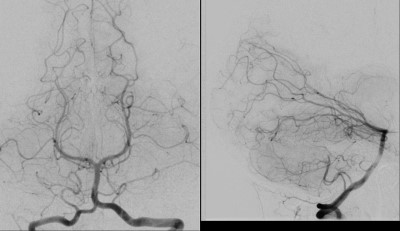

- Pre-Op